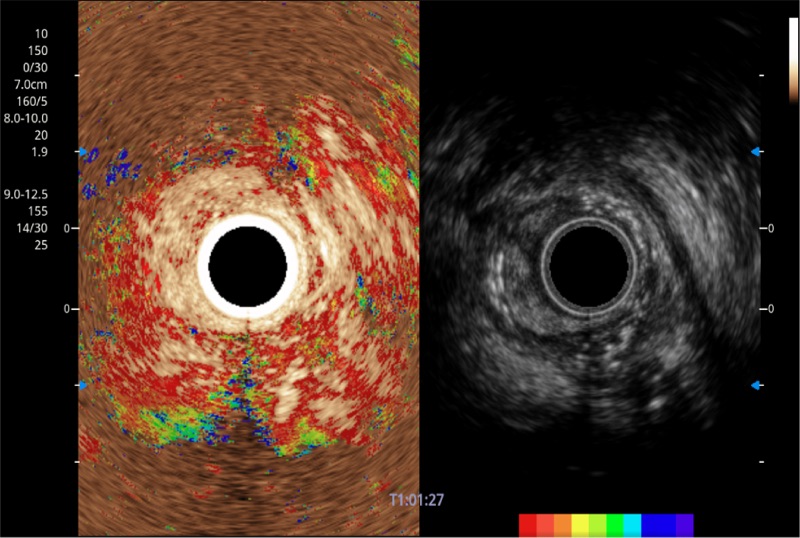

TIC时间强度分析曲线

具有四种造影成像效果

食管内间质瘤清晰显像